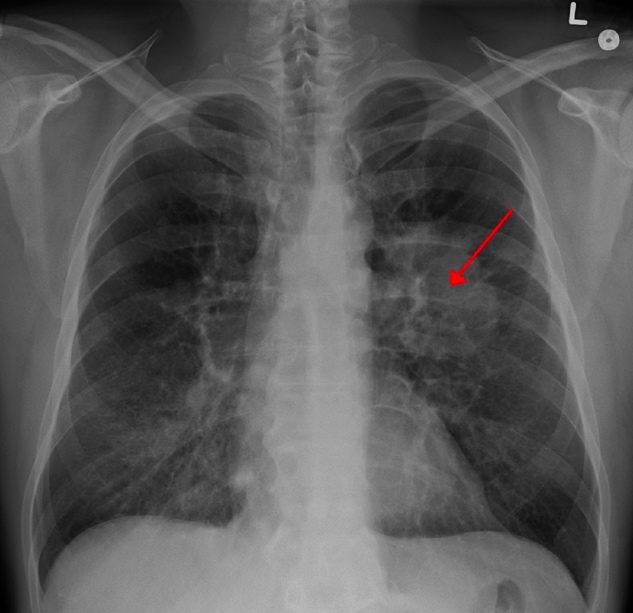

Fig.1 A chest X-ray showing a tumor in the lung (marked by arrow).Distributed under CC BY 3.0, from Wiki.